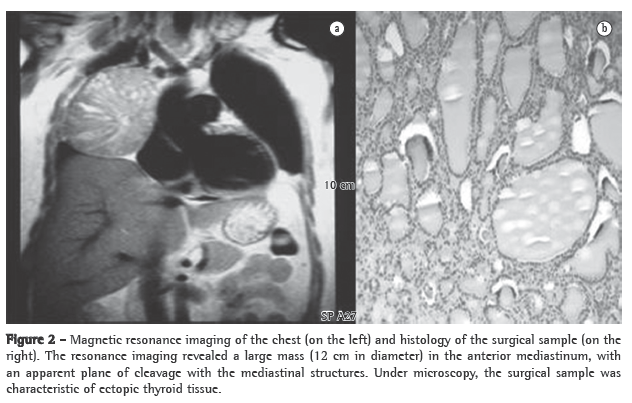

A CT scan of the chest revealed, in the upper mediastinum, a round, extensive formation (4.5 × 4.3 cm), without signs of infiltration and with well-defined borders, located laterally between the superior vena cava and the right contour of the trachea (Figure 3).

The patients underwent excision of the mediastinal tumor (7 × 5 × 4 cm), and the microscopic report of the surgical sample was consistent with intramediastinal thyroid with a macrofollicular pattern and no cellular atypia.